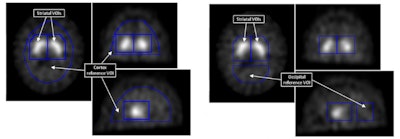

Binding potentials from voxels in striatal VOI were used as features in the support vector machines technique. Cortex and occipital reference VOI were used to calculate them.